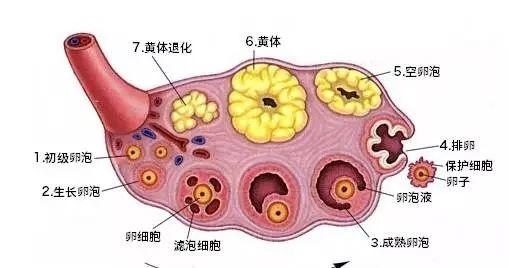

试管婴儿对卵泡有要求吗? 卵泡发育不成熟有可能为卵泡发育不良,卵泡不成熟是属于卵泡发育不良的一种情况,卵泡不成熟,不能正常排卵或者排出的卵子质量不好,都会影响正常...

窦卵泡实际上是卵泡发育过程中发挥承上启下作用的关键环节,与窦卵泡相关的总窦卵泡计数(tAFC)则是评估卵巢储备功能以及评估IVF技术妊娠结果的重要指标。tAFC越...

正常生育年龄妇女每月可有一个卵泡发育成熟并排卵,而在辅助生殖治疗,特别是试管婴儿治疗中,为了在一个月中获得更多的卵子,医生常常会用到超促排卯治疗。超促排卵是指在严...

获得一定数量的优质胚胎是试管婴儿治疗成功的关键,因此获得高质量的卵子是目前临床控制性超促排卵(Controlled ovarian hyperstimulatio...